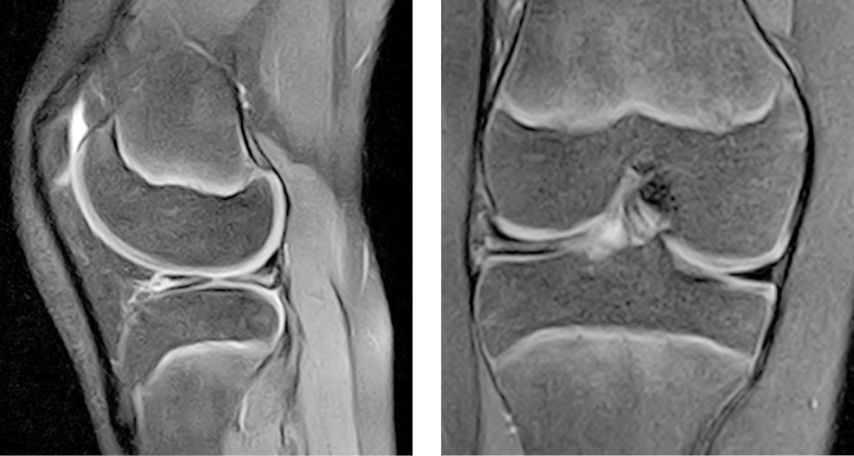

Abb. 2: MRT-Bilder des linken Kniegelenks eines 10-jährigen Jungen mit „bow-tie sign“ in der sagittalen Ansicht in T1-Wichtung

Die Magnetresonanztomografie (MRT) ist eine wesentliche Ergänzung und erlaubt eine genaue Beurteilung der Meniskusmorphologie. Als gängige diagnostische Kriterien gelten eine Breite über 15 mm in frontaler Ebene oder drei aufeinanderfolgende 5-mm-Schnitte in sagittaler Ebene mit Kontinuität zwischen anteriorem und posteriorem Horn (sog. „bow-tie appearance“) (Abb. 2).5 Gerade der inkomplette und der Wrisberg-Typ sind jedoch schwieriger zu erkennen. Hinweisend auf eine vorliegende Instabilität bzw. Hypermobilität können eine Dislokation des posterioren Meniskushorns, eine Faltung und eine höhere Signalintensität in T2 zwischen Meniskus und Gelenkskapsel sein.20,21 Neben der Morphologie gibt die MRT auch wertvolle Zusatzinformationen zu degenerativen Veränderungen und Meniskusrissen. Am häufigsten zeigen sich Horizontalrisse. Hier ist der Meniskus in ein oberes und ein unteres Blatt geteilt (Abb. 3).18

Abb. 3: MRT-Bilder des rechten Kniegelenks eines 12-jährigen Mädchens. Es zeigt sich ein horizontaler Riss in (a) sagittaler und (b) frontaler Ebene in FS-Sequenz